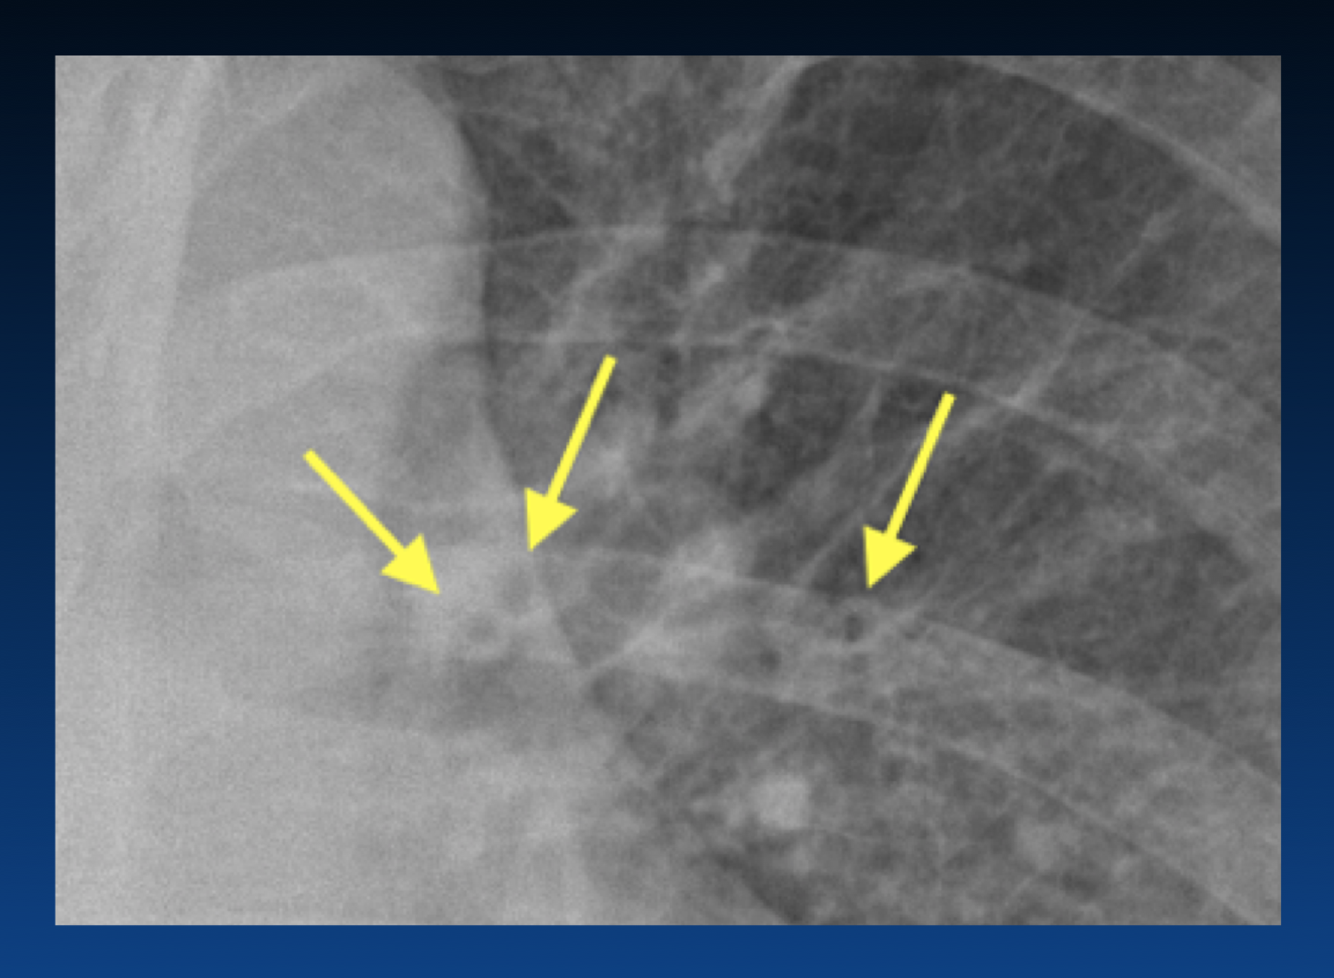

The left atrium is enlarged. What sign is the arrow pointing that indicates this?